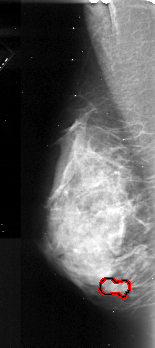

FILE: A_1045_1.LEFT_MLO.OVERLAY

TOTAL_ABNORMALITIES 1

ABNORMALITY 1

LESION_TYPE MASS SHAPE IRREGULAR MARGINS SPICULATED

ASSESSMENT 4

SUBTLETY 3

PATHOLOGY MALIGNANT

TOTAL_OUTLINES 1

BOUNDARY